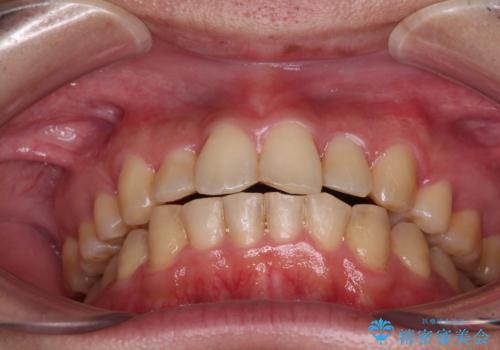

咬合力が非常に強く、抜歯したスペースがなかなか閉じないであろうことは予想できましたが、思っていた以上に期間がかかりました。

前歯のすり減りも著しかったため、仕上げの位置の調整にも期間を要しました。